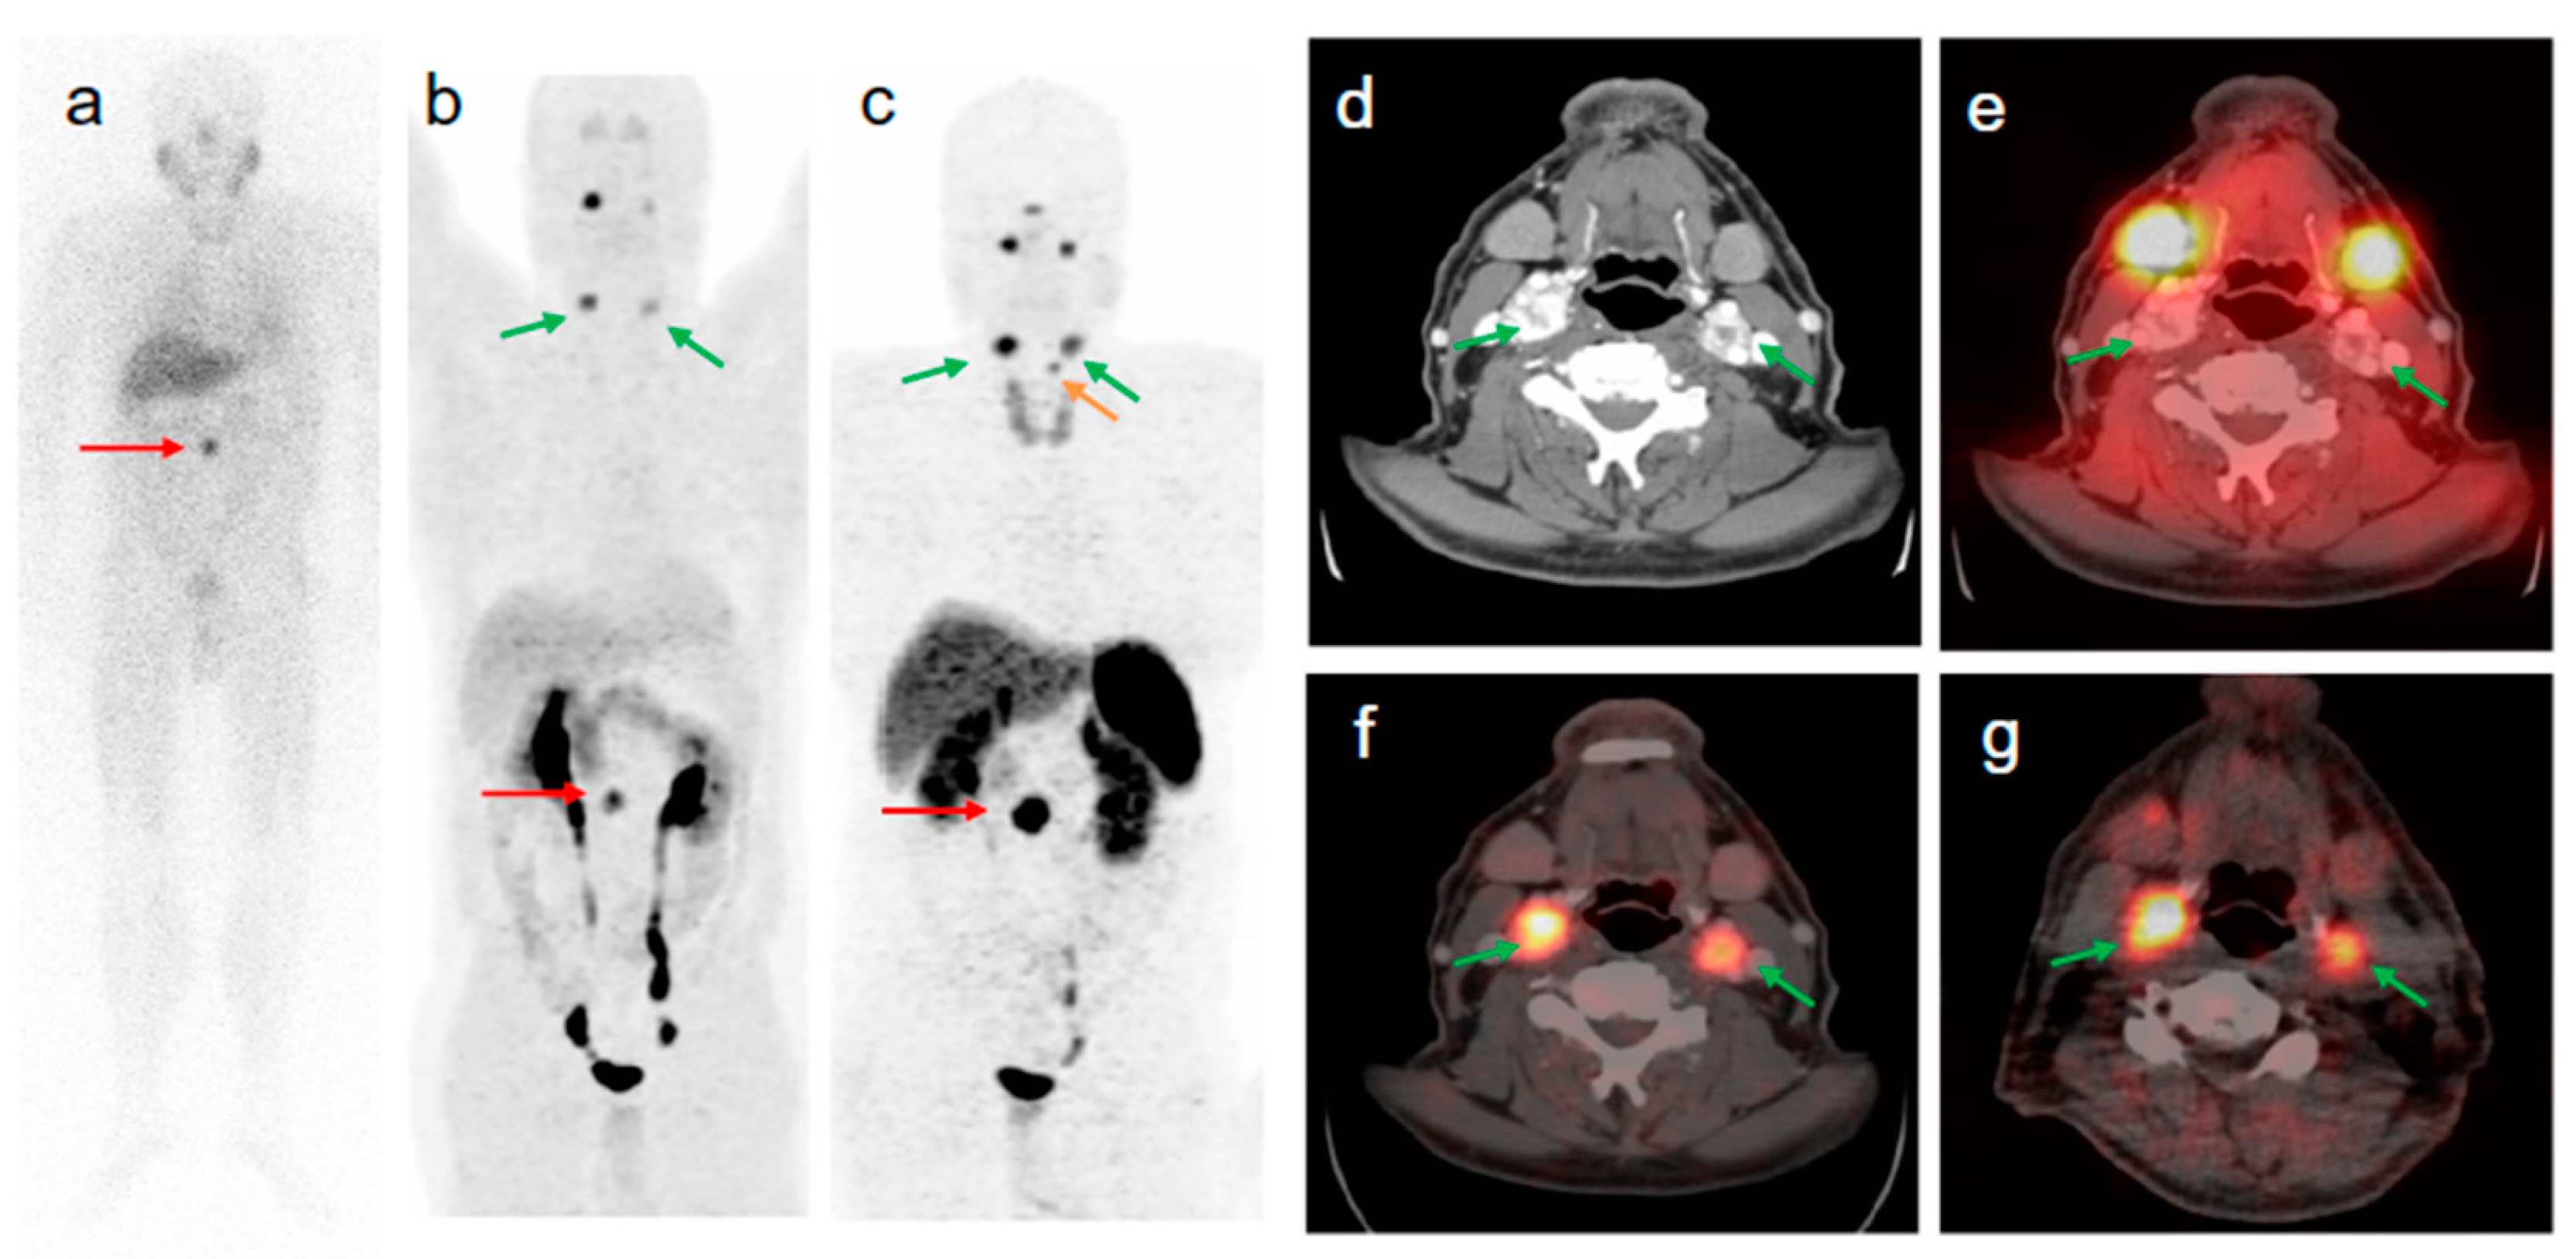

Figure 5.

58-year old male patient with malignant extra-adrenal PGL. The intense focal [123I]MIBG uptake of the abdomen seen on anterior planar image ((a) red arrow) was confirmed by [68Ga]Ga-DOTA-TOC- and [18F]FDOPA PET/CT as being a soft tissue extra-adrenal PGL ((b,c) red arrows). After retrospective software-based image fusion of SPECT images with diagnostic CT images (d), symmetrical physiological [123I]MIBG uptake was observed in the parotid and submandibular glands (a,e). All verified head and neck lesions with focal [68Ga]Ga-DOTA-TOC ((c,f) green arrows) and [18F]FDOPA uptake ((b,g) green arrows) were [123I]MIBG negative (a,e). The small focus of [68Ga]Ga-DOTA-TOC uptake superior to the left upper lobe of the thyroid gland (c orange arrow) is a PGL lesion of the larynx (confirmed by diagnostic CT) which was negative in [18F]FDOPA PET (b). Compared to [123I]MIBG imaging (including SPECT/CT), [68Ga]Ga-DOTA-TOC PET/CT changed the tumor staging from non-malignant to metastatic disease. Reproduced from [43].